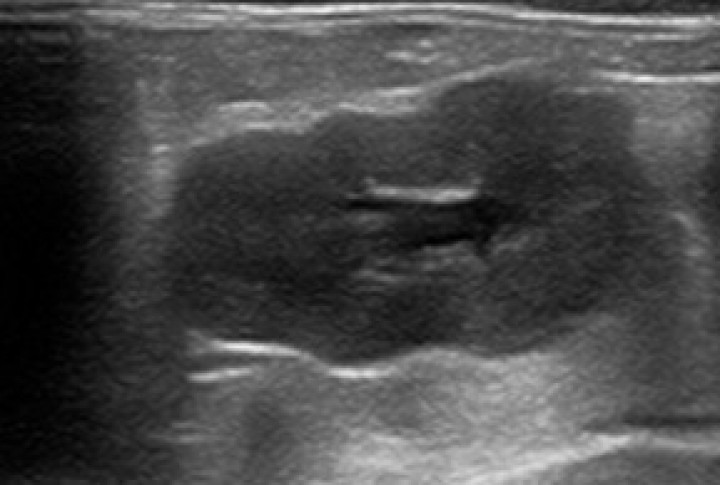

Hurón macho de nueve meses de edad, no castrado, con temblores, debilidad del tercio posterior, mucosas pálidas, pérdida de actividad y de apetito. Presencia de anemia con aumento de urea en la analítica sanguínea, y pérdida de la estructura renal en la ecografía (Fig. 2). En este proteinograma (Tabla 3) también destaca la hipoalbuminemia, aunque no tan marcada como en el caso anterior, y una importante hiperglobulinemia (algo más leve que en el primer caso), con aumento policlonal de γ-globulinas.

<p>Ecografía renal. Alteración de la arquitectura renal en un paciente diagnosticado de enfermedad aleutiana.</p>

Ecografía renal. Alteración de la arquitectura renal en un paciente diagnosticado de enfermedad aleutiana.